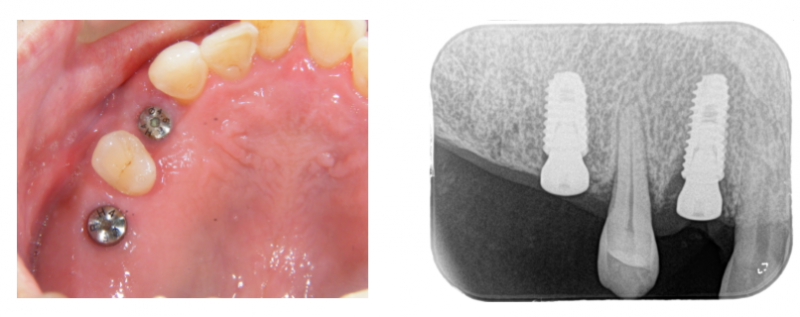

【インプラント症例】抜歯後2週間で埋め込みしたケース

歯周病で、前から4番目の歯がグラグラになっていたので抜歯しました。

このまま放置すると、孤立している1本の歯も時間の問題で抜けてしまいます。

前後に1本ずつ埋め込みする計画になりました。

抜歯直後の部位は、骨量が足りないので、少し骨造成しました。

埋め込みして、3ヶ月待ちました。

3ヶ月待って、歯型を採り上部構造を作ります。

ネジで固定します。